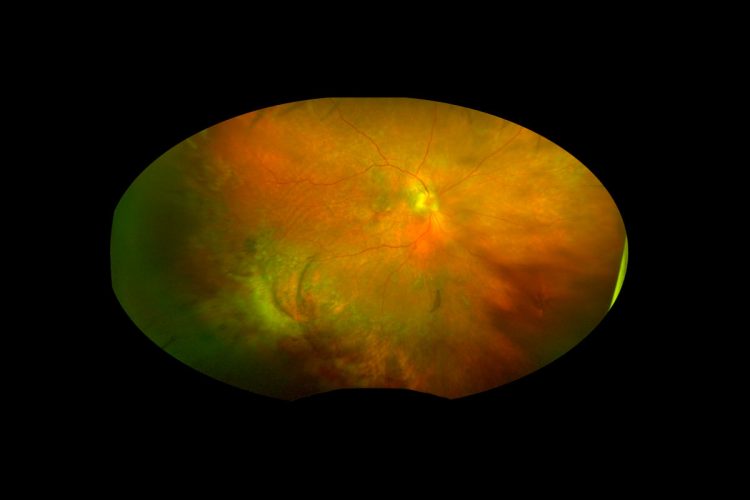

Por los diagnósticos sistémicos encontrados y la lesión coroidea única, se llega a un diagnóstico diferencial de una metástasis coroidea vs una coriorretinopatía exudativa hemorrágica periférica; sin embargo, al no tener la certeza, se decide realizar una vitrectomía diagnóstica 25G. Tras la remoción de la hemorragia vítrea, se observó una masa pigmentada subretiniana en el sector temporal periférico, asociada a desprendimiento exudativo de retina y hemorragia subretiniana (Imagen 3).

Imagen 3